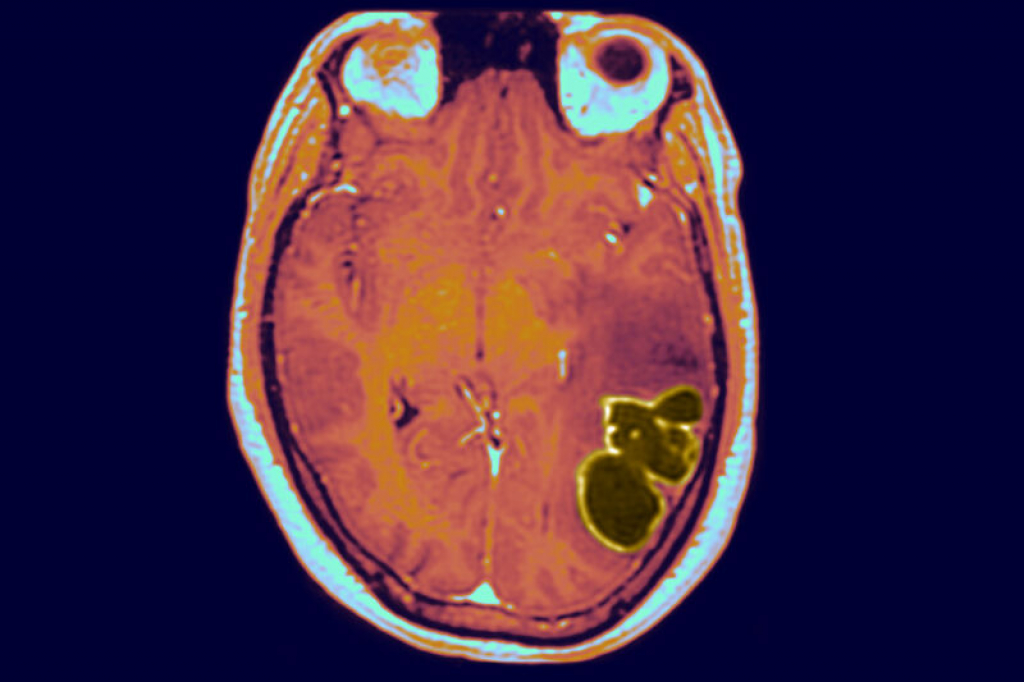

Brain abscesses can be caused by bacteria, viruses, or fungi entering the brain and forming an encapsulated area around the germs and pus. Streptococcus bacteria seem to be the main culprit in the recent rise. The infections can start in several ways, including from an infected head wound, meningitis, and congenital heart disease, but also more common conditions, such as sinus and ear infections. If left untreated, the pockets of pus in and around the brain can lead to rapid deterioration and permanent brain damage, causing severe neurological complications, such as seizures and difficulty with movement, speech, and cognition.

A brain abscess is a pocket of infection that forms within the brain due to bacteria, fungi, or rarely, parasites. A recent study conducted by the Center for Disease Control and Prevention (CDC) suggests that the number of of children in the US diagnosed with a brain abscess has tripled since the beginning of the pandemic. During the first half of 2020, less than 1.2 cases were reported per 100,000 children. In contrast, the new study revealed that during the second half of 2020, more than 3.4 cases were reported per 100,000 children.